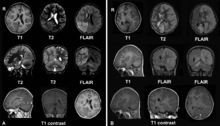

A. December 2008, the patient was presented with headache and epilepsia partialis continua. There are lesions with local brain swelling in the right parietal and occipital lobes and right cerebellar hemisphere.

B. April 2009, the same patient, now she is comatose with epilepsia partialis continua. There is progression of the encephalitis - the left cerebral hemisphere has been involved with severe brain swelling and shift of the midline structures.

The diagnosis may be made on the clinical features alone, along with tests to rule out other possible causes. An EEG will usually show the electrical features of epilepsy and slowing of brain activity in the affected hemisphere, and MRI brain scans will show gradual shrinkage of the affected hemisphere with signs of inflammation or scarring.[8]